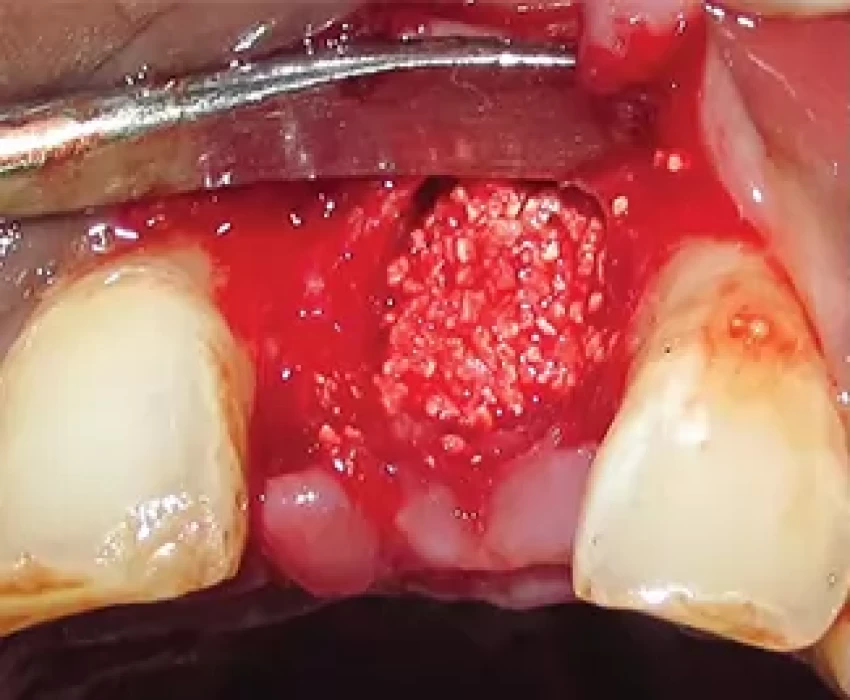

With a rationale for achieving adequate residual ridge that reduces the need for future ridge augmentation to obtain optimal, functional, and esthetic results, this study was conducted to determine the efficacy of PRF and β‑TCP‑Cl in preserving extraction sockets. The resorbable viable bone graft, beta-tricalcium phosphate with type I collagen, has been utilized in orthopedic and other surgical specialties for almost 30 years. During the breakdown and resorption of the graft, no cytotoxic compounds are released and it disintegrate clinically, histologically, and radiographically. It provides a sufficient period to place a dental implant in the grafted site. It is commercially available as a Resorbable Tissue Replacement (RTR) cone (Septodont, Saint‑Maur‑des‑Fosses, France) for the reconstruction of bone defects in maxillofacial and dental surgeries.